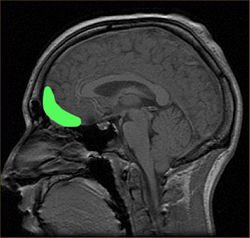

هناك منطقة في الدماغ يُطلق عليها medial prefrontal cortex، وهذه تنشط عندما يفكر الانسان بنفسه، وبشكل أخص حين يكون هذا التفكير تفكيرا مرتبط بالاحاسيس والمشاعر.

هذه المنطقة تنشط بشكل كبير في المواقف الاجتماعية التي يتعرض لها الانسان اذا ما كانت هذه المواقف تحمل دلالة متعلقة بمشاعر.

تبلغ هذه المنطقة قمة نشاطها عندما يكون الانسان بعمر ال١٥.

بالنسبة للمراهق فإنّ مراقبة الاخر له تحمل وزن كبير على مستوى الاحساسيس والمشاعر وتخلق حالة هيجان نفسي له، على عكس البالغ الذي قد لا يعير ذلك اهتمام كبير.

السبب في ذلك بأنّ المراهق في هذه الفترة من عمره يعير عملية "التفكير بنفسه" "والتقييم الذاتي" اهتمام كبير، بينما البالغ قد يكون تجاوزها وتشكّل طابعه العام عن نفسه.

لهذا السبب فإنّ المواقف الاجتماعية تثير انفعالات أشد قوة عند المراهق، لأنه يقيّم ذاته من خلالها! ونجد ذات واضحا في ازدياد نشاط منطقة الmedial prefrontal cortex.

٤) كل بضعة اسابيع تتبدل خلايا جلودنا، وكل اربعة شهور، تكون كل خلايا الدم الحمراء قد تبدلت. وفي سبع سنين، كل ذرات جسمنا تكون قد تبدلت، وبالتالي نحن عمليا - بعد هذا التبدل - مختلفين عمّا كنّاه قبل التبدل.

فما هو الشيء الذي يجمعنا في كيان واحد .. ما هو الشيء الذي يربط كل هذه الشخوص والاعمار المختلفة في كيان واحد؛ إنها الذاكرة.

لوهلة قد نحسب أنّ هذه الحقيقة تجعل من الذاكرة شيئا قويا باعتبارها تجمع كيانات الفرد المختلفة في وحدة واحدة، ولكننا حين نختبر هذه الذاكرة، ندرك هشاشتها.